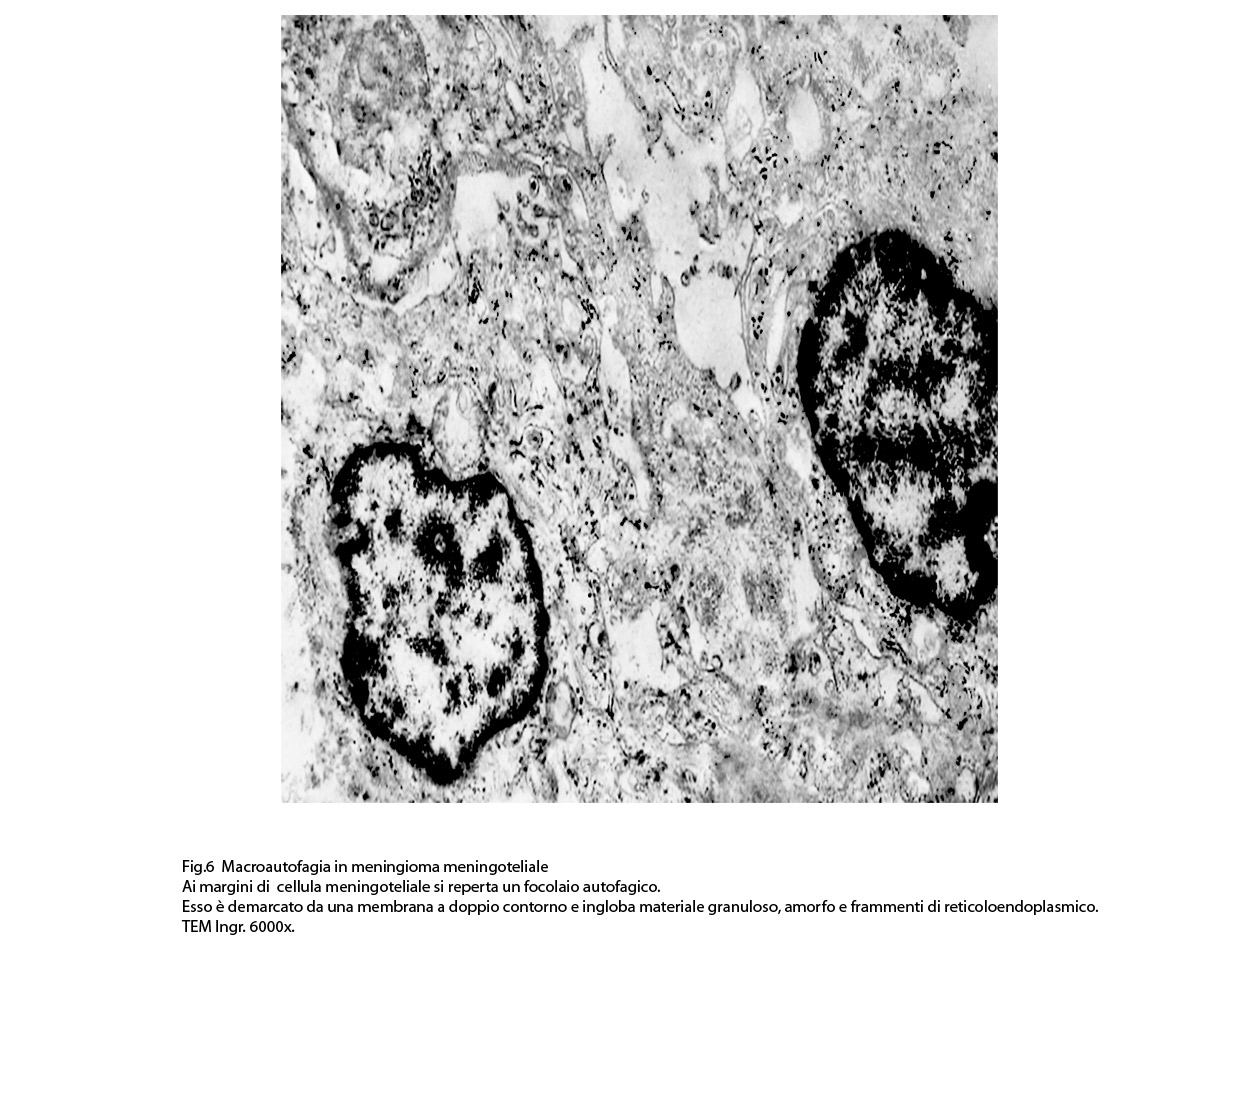

2) MACROAUTOFAGIA

La macroautofagia ,come sopra è stato fatto cenno,è un processo che si manifesta per stadi evolutivi; di questi, due sono, sul piano ultrastrutturale, diversi e sono indicati quali autofagosomi e auto lisosomi; pertanto la loro presentazione richiede i seguenti due distinti paragrafi:

2/a AUTOFAGOSOMA

I focolai di macroautofagia possono essere presenti in zone diverse del citoplasma. La loro microstruttura di base è costituita da una area vacuolare demarcata da una membrana a doppio strato; l’area cava è occupata per quote variabili da materiale amorfo,da aggregati filamentosi,da frammenti di organuli,da gruppi granulosi, il tutto in diversi stati di conservazione. Questi focolai macroautofagici appaiono come strutture avulse dalle mutevoli condizioni bio-morfologiche del citoplasma nel quale si sono formate. E’ frequente il riscontro di cellule di aspetto cribroso per la esistenza di micro vacuoli scavati nel citosol e per la dilatazione delle cisterne del reticolo endoplasmico contengano nel citosol una formazione macroautofagica occupata in parte da materiale amorfo e filamentoso.

Sono repertabili anche cellule meningoteliali ben strutturate e ricche di organuli marcate da un focolaio di autofagia contenente frammenti di substrutture e materiale filamentoso.